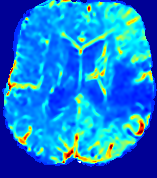

LesionRefer to captionRefer to captionRefer to captionRefer to captionRefer to captionRefer to caption𝐕rgbsubscript𝐕𝑟𝑔𝑏{\bf{V}}_{rgb}Refer to captionRefer to captionRefer to captionRefer to captionRefer to captionRefer to caption𝐕2subscriptnorm𝐕2{\|\bf{V}}\|_{2}Refer to captionRefer to captionRefer to captionRefer to captionRefer to captionRefer to captionRefer to caption3.53.53.52.82.82.82.12.12.11.41.41.40.70.70.70.00.00.0(mm/s)𝑚𝑚𝑠(mm/s)D𝐷DRefer to captionRefer to captionRefer to captionRefer to captionRefer to captionRefer to captionRefer to caption0.0200.0200.0200.0160.0160.0160.0120.0120.0120.0080.0080.0080.0040.0040.0040.0000.0000.000(mm2/s)𝑚superscript𝑚2𝑠(mm^{2}/s)Slice #1Slice #2Slice #3Slice #4Slice #5Slice #6

Figure 3: PIANO feature maps for one stroke patient, where the lesion is located in the left hemisphere. Top row: segmented stroke lesion region (white) on different slices, obtained from ISLES 2017. The corresponding slices for the PIANO feature maps are shown in the following rows.

For a better insight into an estimated velocity field 𝐕𝐕{\bf{V}} and diffusion field 𝐃𝐃{\bf{D}}, we compute the following maps: (1) 𝐕rgbsubscript𝐕𝑟𝑔𝑏{\bf{V}}_{rgb}: Color-coded orientation map of 𝐕=(Vx,Vy,Vz)T𝐕superscriptsuperscript𝑉𝑥superscript𝑉𝑦superscript𝑉𝑧𝑇{\bf{V}}=(V^{x},V^{y},V^{z})^{T}, obtained by normalizing 𝐕𝐕{\bf{V}} to unit length and mapping its 3 components to red, green, blue respectively; (2) 𝐕2subscriptnorm𝐕2\|{\bf{V}}\|_{2}: 222 norm of 𝐕𝐕{\bf{V}}; (3) D𝐷D: scalar field in Eq. 5.

Fig. 3 and Fig. 4 show the PIANO feature maps estimated from two ISLES 2017 patients: all are highly consistent with the lesion in both cases. Details of the blood flow trajectories are revealed in 𝐕rgbsubscript𝐕𝑟𝑔𝑏{\bf{V}}_{rgb} by the ridged patterns and the sharp changes of colors in the unaffected (right) hemisphere, while the flat patterns appearing within the lesion provide little directional information about the velocity and indicate low velocity magnitudes. Velocity magnitudes are more directly visualized via 𝐕2subscriptnorm𝐕2\|{\bf{V}}\|_{2}, from which one can easily locate the lesion where 𝐕2subscriptnorm𝐕2\|{\bf{V}}\|_{2} is low. D𝐷D also indicates lower diffusion values in the lesion, though with less contrast potentially due to the fact that it captures the accumulated effect of CA diffusion at the voxel-level.